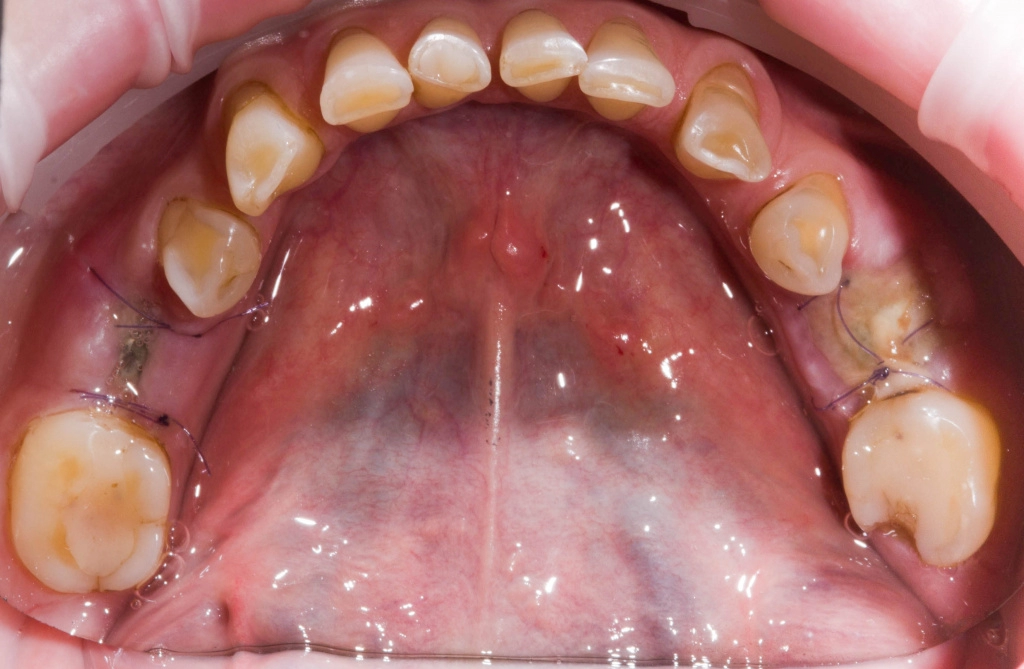

Удалены корни 3.6, 4.6, с одномоментной установкой имплантатов 3.6, 4.6 и забором соединительно-тканного трансплантата с небной поверхности в области 1.6.